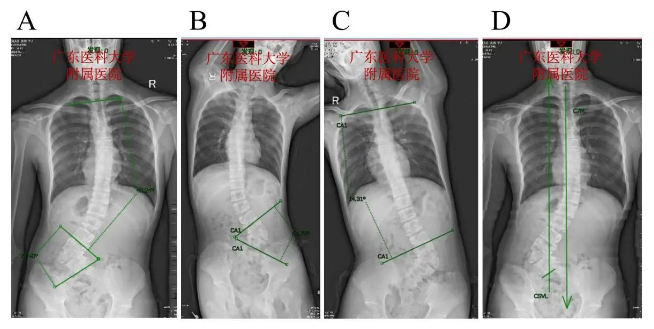

A图. 脊柱全长片正位片,胸椎可见13个椎体及肋骨,拟先天变异,胸弯以胸8为顶锥向右侧凸,胸腰弯(T2-L2)Cobb角49.24°;L4为半椎体,腰弯以L4半椎体为顶锥向左侧凸,腰弯(L3-L5)Cobb角73.40°。

B图.仰卧位左侧Bending像腰弯(L3-L5)Cobb角64.73°。

C图. 仰卧位右侧Bending像,胸腰弯(T2-L2) Cobb角14.31° 。D图. 骶骨中垂线(CSVL)和颈7铅线(C7PL)